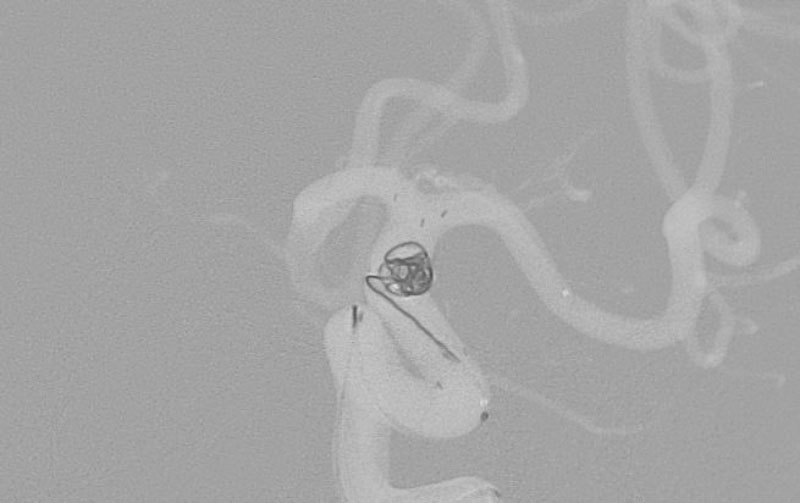

No.1596 手術中